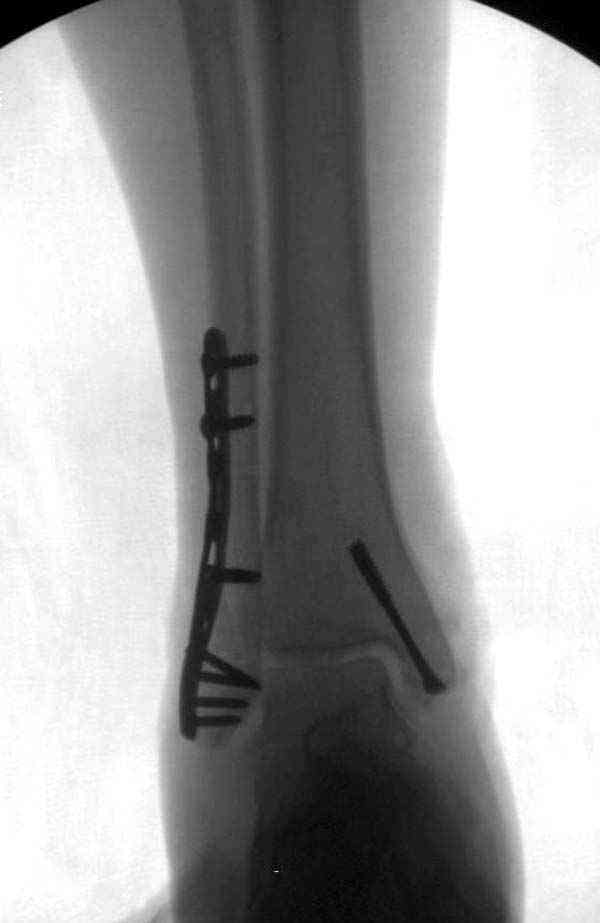

Описанная вами техника "Внутренняя лодыжка фиксирована по Веберу, наружная реконструктивной пластиной с наложением болта-стяжки" существует, но этот подход морально устарел, и применяется очень редко, только при отсутствии имплантов.

Реконструкционные пластины на лодыжке очень грубые, и из-за тонкого слоя кожи над дистальным концом малоберцовой могут осложниться пролежнями кожи изнутри.

Нет первичных снимков, перелом очень низкий и под большим сомнением диагноз разрыва синдесмоза. Медиальная сторона отрепонирована на "хорошо" и, по-видимому, прорезание проволоки произошло во время операции. Без снимков трудно судить о высоте малоберцовой, а лодыжка находится в варусе. Лагирование получилось, но возле тонких шурупов передне-задний шуруп выглядит немного тяжеловато.

Во всех руководствах АО имеется описание техники применения низкопрофильных пластин 1/3 трубки, которые могут быть применены для фиксации наружной лодыжки. Фиксацию проводят кортикальными 3.5 мм шурупами, и если дистальная фиксация недостаточная, тогда усиливают конструкцию созданием hook plate. Сгибая конец пластины на последнем отверстии, внедряют его в дистальный отдел, и тем самым создается дополнительная фиксация.

Современные преконтурированные пластины не имеют таких недостатков, и разделяются на правые и левые, а также на латеральные и задние. Множественные дистальные шурупы 2.7 мм уменьшают подкожное раздражение, и такой имплант можно оставить на долгий срок без удаления.

Для молодых достаточным бывает обычная лодыжечная пластина без блокировки, и только у пожилых с остеопорозом лучше взять полиаксиальные пластины с угловой стабильностью.

Здесь несколько частных случаев: перелом голеностопа со сравнительными снимками и разрыв синдесмоза, а также медиальная Hook пластина.